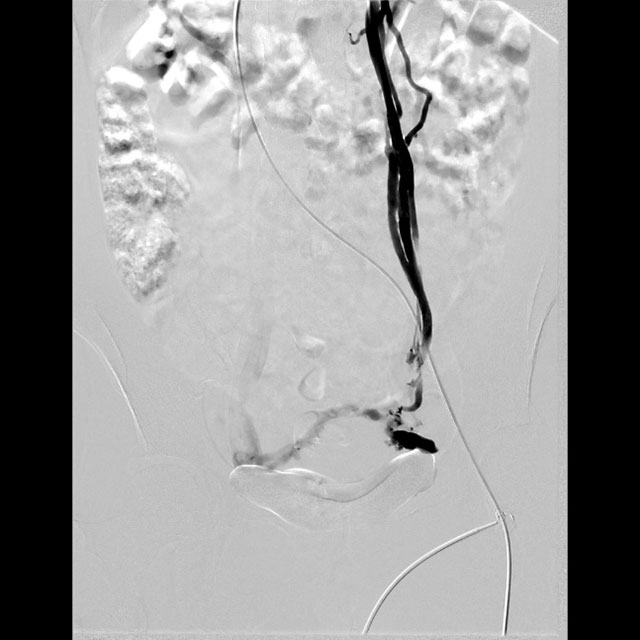

△栓塞前DSA造影提示:卵巢静脉返流、迂曲

入院后,超声检查进一步明确 “盆腔内探及曲张静脉”。介入・血管科徐燕能博士团队结合检查结果,为其制定了周密的介入手术方案 ——卵巢静脉造影 + 栓塞术。术中栓塞前的 DSA 造影显示,王女士存在 “卵巢静脉返流、迂曲” 的典型病变;而经过硬化、栓塞治疗后再次造影,卵巢静脉返流现象完全消失。